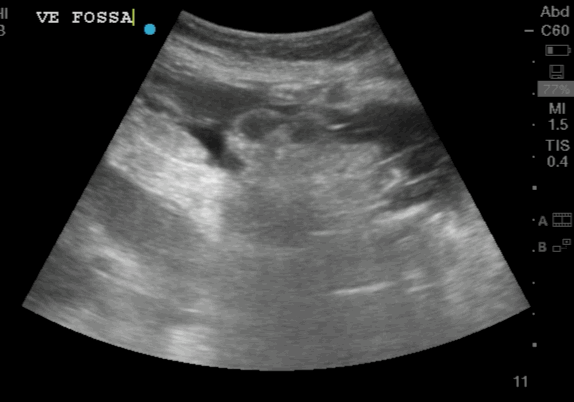

The video clip shows a small rim of free fluid along the liver edge with extensive free fluid noted amongst the intestinal loops

Free Fluid Around the Intestinal loops

Free Fluid in between the Intestinal loops